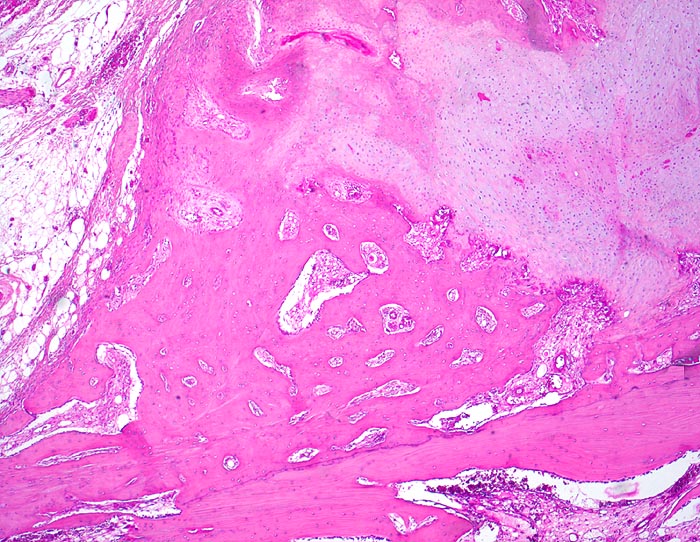

sekundäre Frakturheilung: Kallus

Knochen, Rippe

Dem Frakturspalt aussen aufsitzender knöcherner und knorpliger Kallus mit Zonen der enchondralen Ossifikation. Extraperiostales Fettbindegewebe.

Konservativ behandelte Rippenfraktur nach Sturz vor einem Monat.

Die Frakturenden werden durch den Kallus überbrückt. In der Frühphase der Heilung wird ein Übermass an Bindegewebe, Knorpel und Knochen gebildet vor allem bei ungenügender Ruhigstellung. Während der Ausreifung des Kallus werden diejenigen Gewebsanteile, welche keiner erhöhten Belastung ausgesetz sind, wieder resorbiert. Der Kallus wird im Verlauf der Zeit zunehmend kleiner.